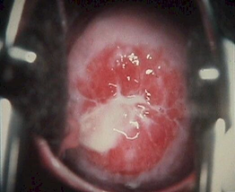

Signs & symptoms: Vulval itching, frothy yellowish green discharge, dysuria, strawberry cervix. Diagnosis: